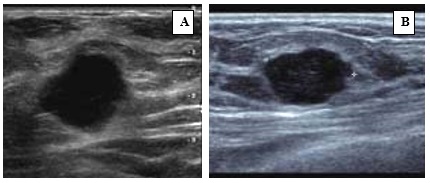

Características radiológicas en ecografía

En la investigación bibliográfica de las características de imagen en CMTN, se ha encontrado que en la ecografía la mayoría de las lesiones se manifiestan como nódulos o masas hipoecoicas solitarias, con contornos lobulados o mal definidos, y ocasionalmente presentan sombra acústica.

Además, otras investigaciones similares respaldan estos hallazgos. Se encontró que en un alto porcentaje de casos (hasta el 92%) el CMTN se presentó como nódulos, y en un 7,2% de los casos se manifestó como otra lesión. La gran mayoría de estos nódulos presentaron características hipoecoicas, con una forma ovalada predominante (49,2%). En cuanto a los márgenes, la mayoría de los nódulos tenían márgenes microlobulados (39,7%), y solo un 4% presentaron márgenes espiculados.

Al analizar los hallazgos acústicos posteriores, el refuerzo acústico posterior se destacó como uno de los hallazgos más relevantes, con un 35,5% de los casos. También es común observar que la vascularización de estas lesiones tiende a ser de predominio periférico o ausente. Sin embargo, en un pequeño porcentaje (5%) de los casos, las lesiones pueden pasar desapercibidas en los estudios de ultrasonido.(5, 19, 22, 23, 24, 25, 26, 27)

En la ecografía estos tumores pueden parecer lesiones de morfología benigna, ya que se manifiestan como nódulos sólidos, redondeados, con márgenes circunscritos, hipoecoicos, con refuerzo posterior y con vascularización periférica.

En ecografía evidenciaron que se expresa como nódulo redondeado u oval, de márgenes circunscritos, hipoecoico con refuerzo acústico posterior en algunas ocasiones categorizado como BI-RADS 3. En resonancia magnética se visualizaron como nódulos de márgenes irregulares, con realce nodular poscontraste en anillo, con curvas anormales en fase tardía tipo “wash out”.

Características ecográficas del CMTN

Los resultados de las características ecográficas revelan los siguientes hallazgos en la investigación. Se describe la forma del nódulo de la siguiente manera: en su mayoría es ovalado (n = 13,76%), con márgenes microlobulados (n = 7, lo que corresponde al 41%), seguido de márgenes circunscritos (n = 5, equivalente al 29%). Además, se observa que son hipoecoicos (n = 16, lo que corresponde al 94,2%) y se ubican de manera paralela al eje cutáneo (n = 15, equivalente al 88,2%).

En relación con los hallazgos acústicos posteriores, se destaca que 14 pacientes, que conforman el 82% del grupo, no presentaban hallazgos acústicos ni calcificaciones intra ni extra nodulares.

En cuanto a la vascularización, se observa que en 14 pacientes (equivalente al 82%) no se detectó vascularización en el estudio realizado con Power Doppler. En contraste, 3 pacientes presentaban vascularización periférica, representando el 17,6% de la muestra. En ninguno de los casos se informó distorsión arquitectural ni cambios cutáneos. Sin embargo, en 15 pacientes se observaron adenopatías axilares, lo que corresponde al 88,2% del grupo estudiado.

Anexo 2. Imágenes ecográficas del CMTN